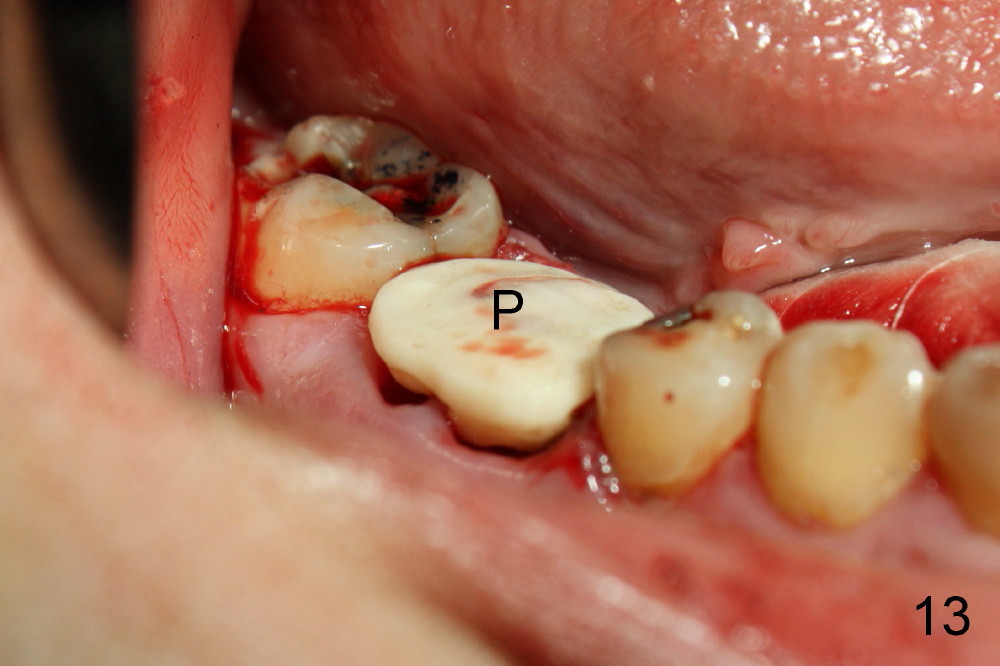

A 38-year-old lady agrees to have implant placement 7 years after loss of the crown of the lower right first molar (Fig.1,2). When the tooth is extracted, the septum is found to be low (Fig.3,4). To confirm it, a PA is taken (Fig.5). To initiate an osteotomy in the septum, it is trans-sectioned with thin osteotomes as shown in Fig.4 insert (black line). A 2 mm pilot drill is placed in the septum (Fig.6: P). The osteotomy is enlarged by 2.5-4.0 mm reamers (Fig.7,8), followed by insertion of 6x17 mm tapered tap at the depth 14 mm (Fig.9). The osteotomy is further enlarged by 4.5 and 5.0 mm reamers. A 6.0x14 mm one piece implant is placed initially. The trajectory is not ideal. A 6.0x14 mm one piece implant is placed initially. The trajectory is not ideal. The implant is removed from the osteotomy partially and reinserted with improved trajectory (Fig.11, compare to Fig.10 (red line)). Primary stability is high. There is not much bone mesiodistally so that the trajectory is easily changed in that direction. After abutment preparation, mixture of autogenous bone (harvested from reamers) and allograft is placed in the residual mesial and distal sockets (Fig.12). To contain the bone graft, an immediate provisional is placed (Fig.13 P). The occlusal plane of the provisional is significantly lower than that of the adjacent teeth to avoid micromovement of the implant. The patient is advised to eat soft food on the left side. Six days postop, the patient returns for prophy. The provisional is removed; the bone graft appears to be incorporating into the socket (Fig.14). After recementation, the provisional remains in place for 3.5 months; PA shows increased bone density in the mesial and distal sockets (Fig.15, compare to Fig.5,11). Due to insurance coverage, the patient defers fabrication of definitive restoration for at least 7 months. The immediate provisional is finally lost 8.5 months postop: the gingiva attaches to the 1-piece implant (Fig.16), while the density of the mesial socket increases (Fig.17 *) with formation of the cortex (lamina dura) coronally (v). Before the provisional (Fig.18 P) is removed for cementation of the definitive restoration, black shadow (*) is noted over the buccal gingiva. It is partially due to buccal placement (Fig.19) and partially due to buccal atrophy over a period of 10.5 months postop. How to prevent buccal placement? Positioning the first pilot drill in the septum buccolingually is a key. Eleven months post crown (Fig.20 C) cementation, the black shadow remains, but there is no tenderness. If the implant threads are immediately underneath the periosteum, there is tenderness.